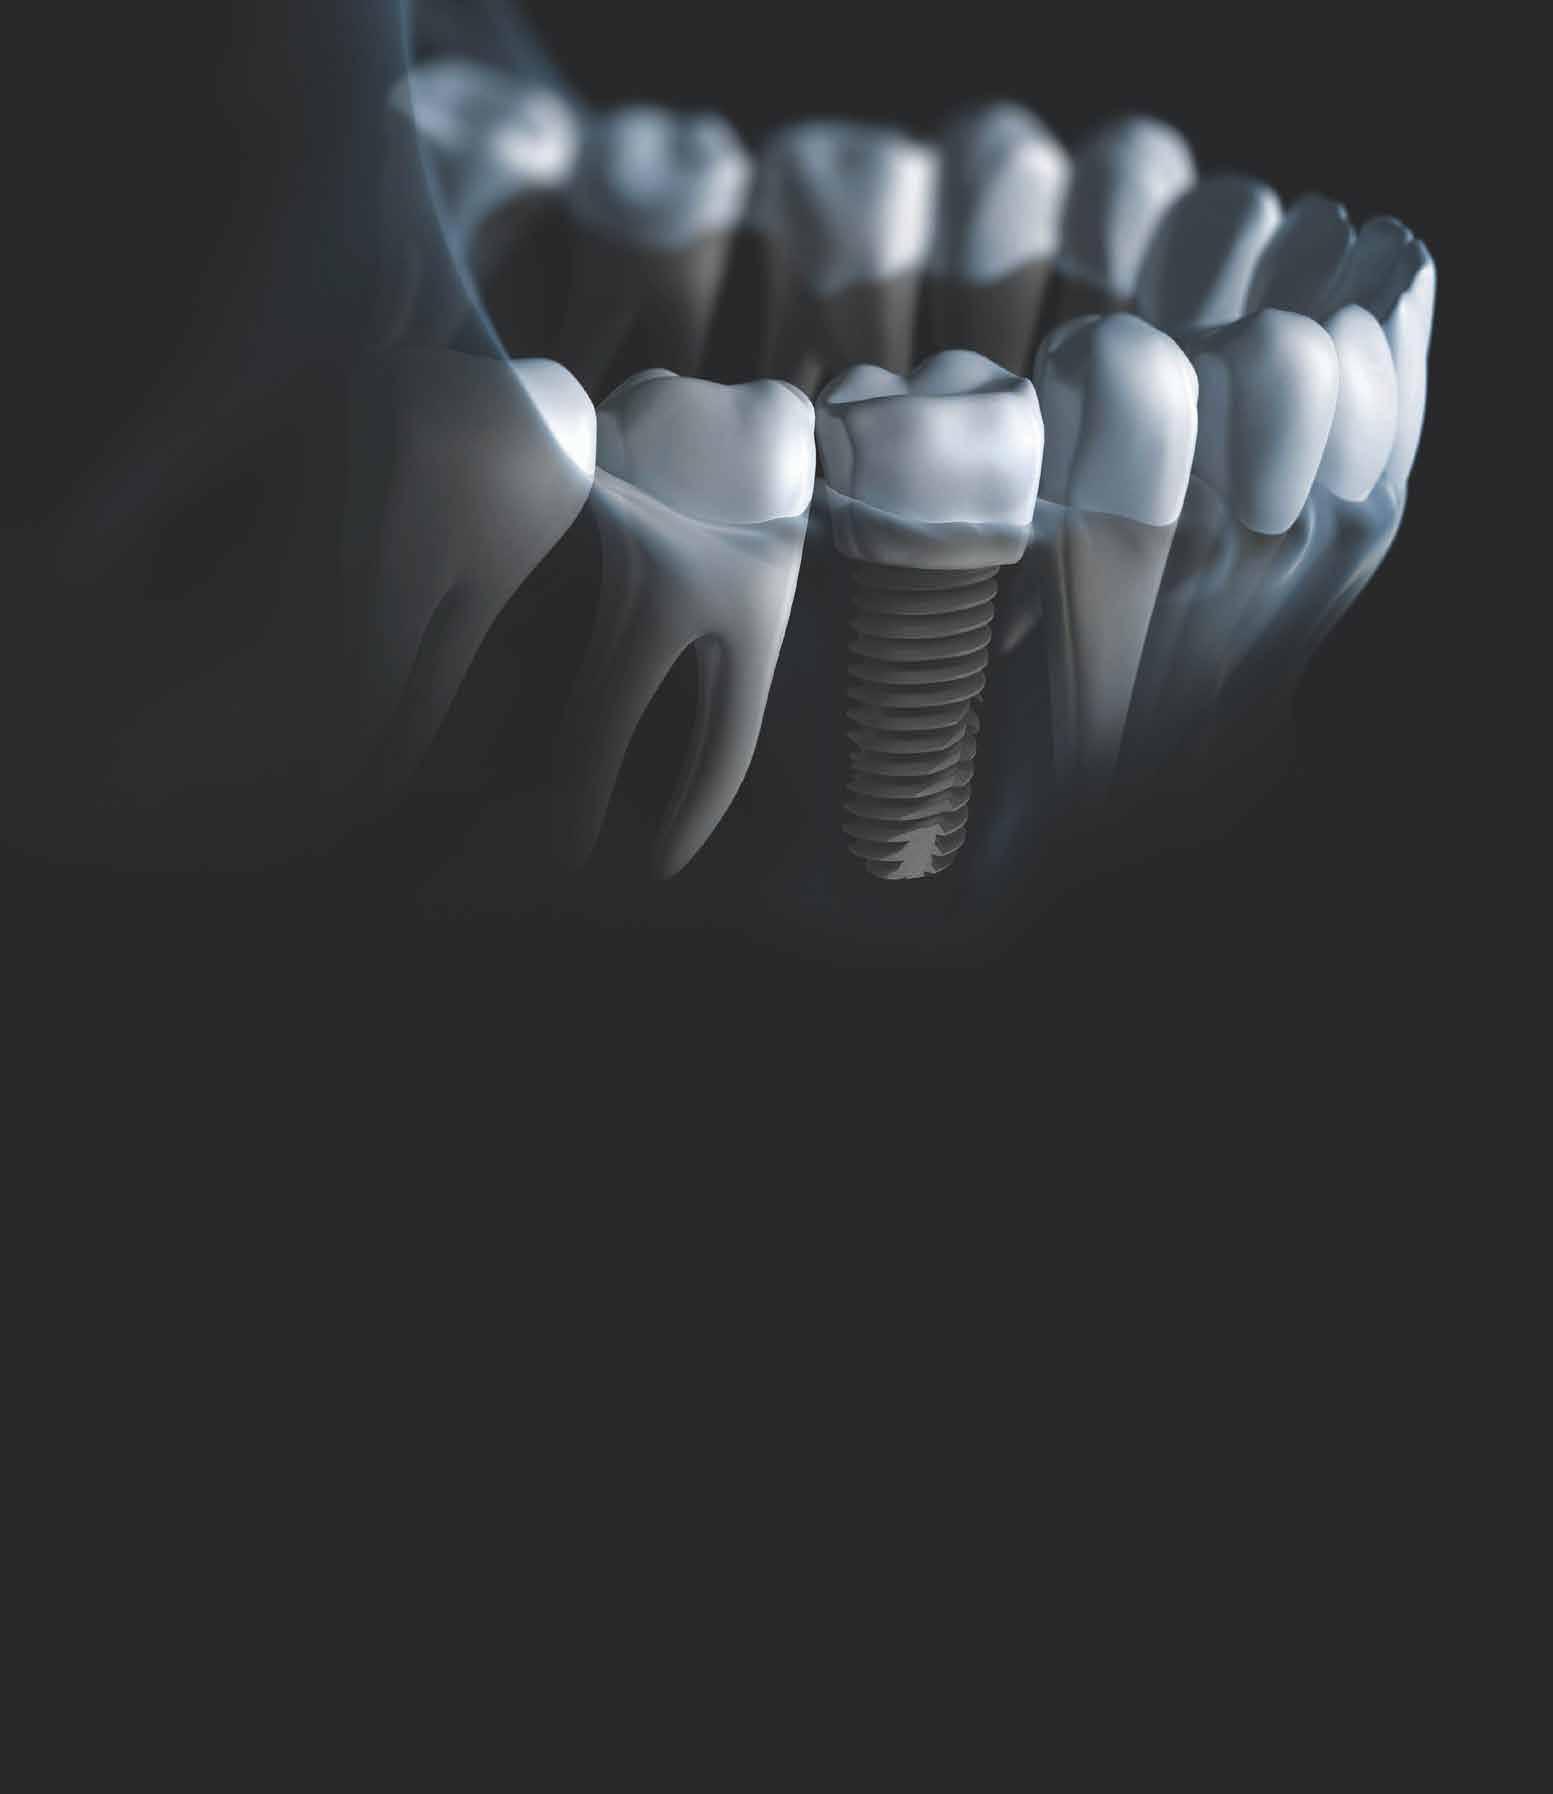

A felső frontrégió helyreállítása mind sebészi, mind protetikai szempontból kihívást jelentő feladat. A funkció és a megfelelő esztétikai eredmény elérése már a tervezés első pillanatától kiemelkedő fontossággal bír, az implantológia utóbbi évtizedekben tapasztalt fejlődése azonban egyre jobb és kiszámíthatóbb alternatívákat kínál. Jelen esetbemutatásunkban egy korábbi balesetben sérült, jobb felső nagymetsző fog helyreállítását szeretnénk ismertetni, egyéves utánkövetéssel.

behelyezését, majd csavarozott rögzítésű, cirkónium-dioxid vázas, kerámialeplezésű korona készítését terveztük [1., 5., 6., 8.].

A tíz évvel ezelőtt még csak az állatkísérletekben leírt, azóta azonban már humán kutatásokban is vizsgált és napjainkban már széleskörűen alkalmazott, socket-shield technika alkalmazását tartottuk a legjobb választásnak [2., 4., 7.]. Az azóta megjelent szakirodalmi adatok alapján, a fent említett módszer alkalmas a bukkális oldal kemény- és lágyszöveti kontúrjának megőrzésére, a funkció mellett a megfelelő esztétikai eredmény elérésére is [3.].